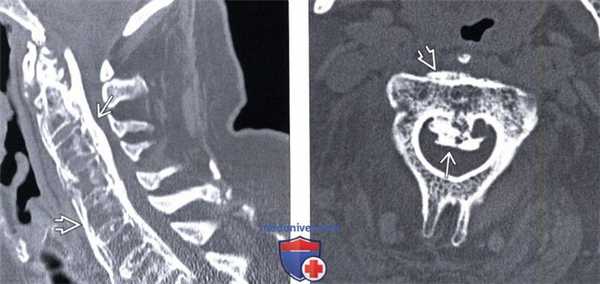

(Слева) КТ, сагиттальный срез: протяженная и равномерная оссификация ЗПС, вызывающая тяжелый стеноз спинномозгового канала. Видны также признаки оссификации и ППС на фоне тяжелого анкилозирующего спондилита.

(Справа) КТ, аксиальный срез: массивная в форме «перевернутой буквы Т» оссификация ЗПС, приводящая к тяжелому стенозу спинномозгового канала на уровне С2. Также видны признаки типичной для анкилозирующего спондилита оссификации ППС.г) Патология: